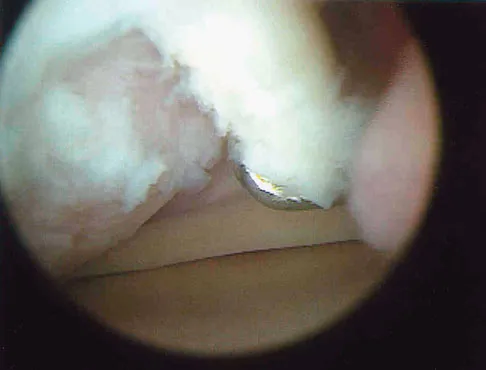

A 30-year-old patient reports chronic medial knee pain and swelling. Figure 9a shows an articular cartilage lesion observed during arthroscopy. The surgeon decides to treat the lesion with the microfracture technique seen in Figure 9b. A biopsy of the repaired tissue 1 year after treatment is likely to show which of the following findings?